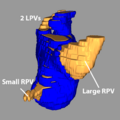

- Carma 3RPV.png 600 × 555; 148 KB

- Carma 3RPVs.png 600 × 555; 148 KB

- Carma 4RPV.png 600 × 600; 193 KB

- Carma 4rpvs.png 600 × 600; 165 KB

- Carma Com LPV.png 599 × 524; 122 KB

- Carma Norm LPVs.png 651 × 631; 138 KB

- Carma Norm RPVs.png 593 × 551; 115 KB

- Carma RPVs small.png 610 × 610; 130 KB